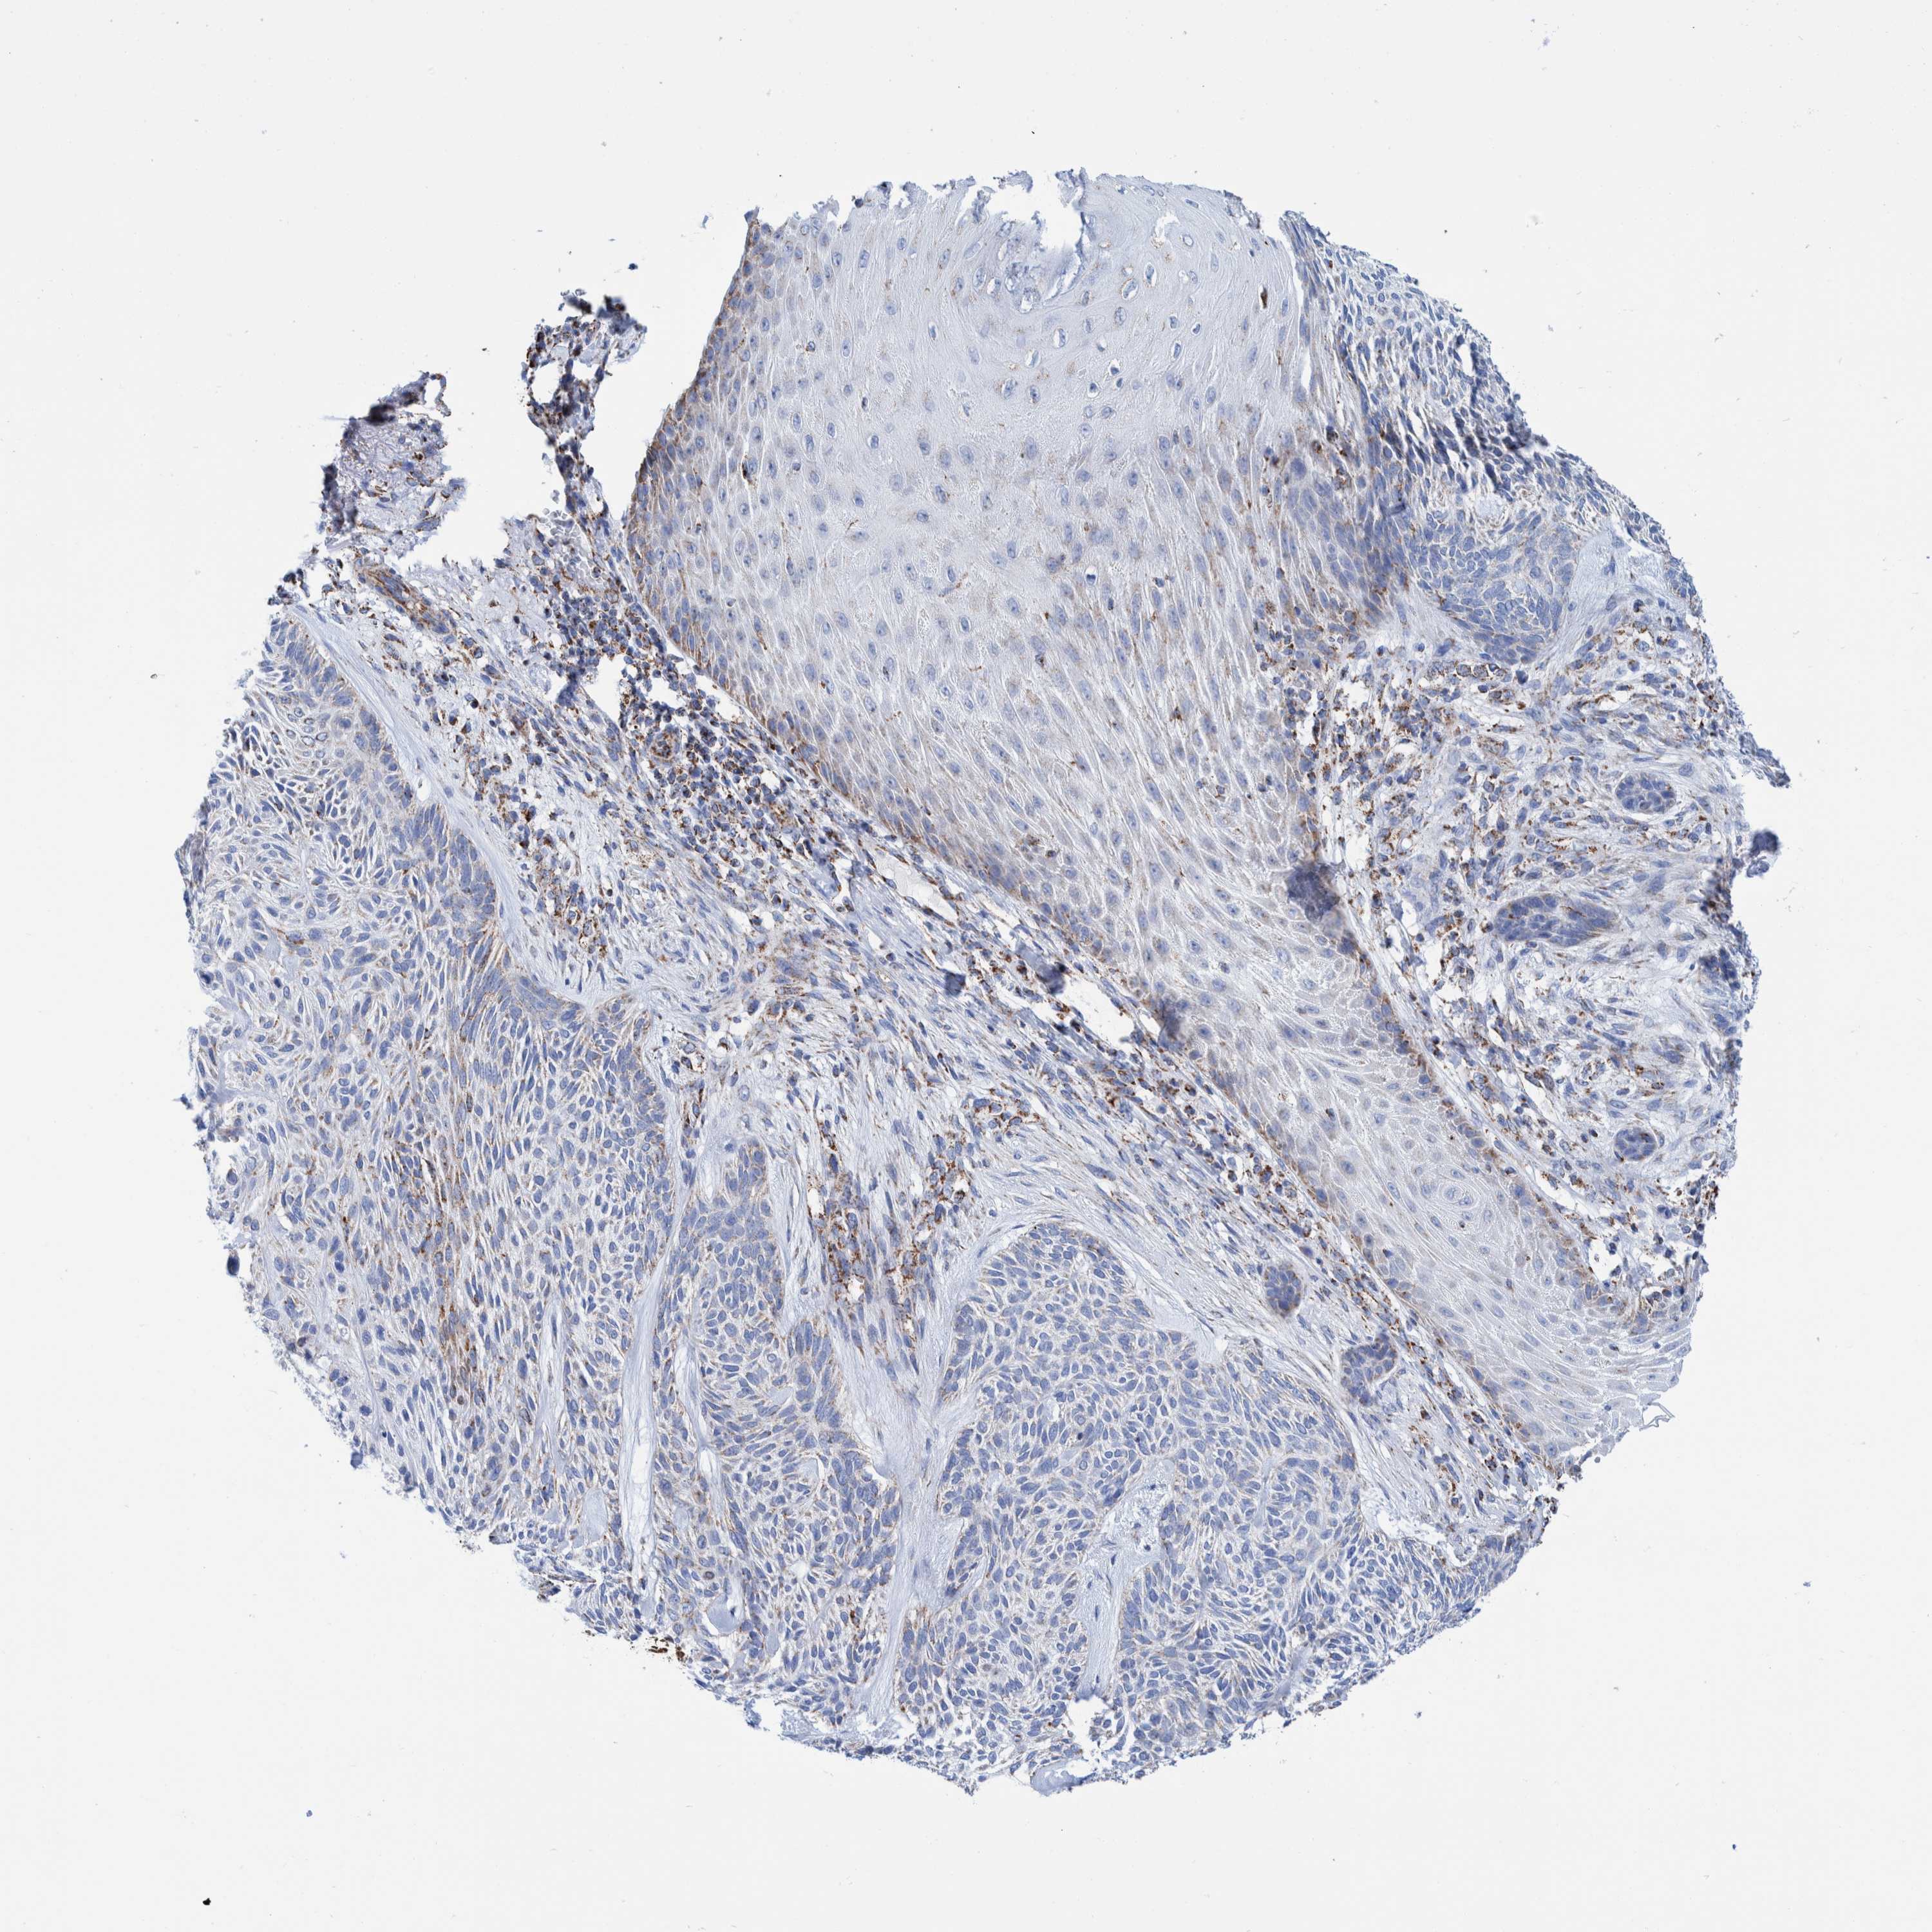

SKIN CANCER - Protein expressioni

A mouse-over function shows sample information and annotation data. Click on an image to view it in a full screen mode. Samples can be filtered based on level of antibody staining by selecting one or several of the following categories: high, medium, low and not detected. The assay and annotation is described here.

Each image is clickable and will lead to virtual microscopy that enables deeper exploration of all samples and also displays staining intensity scores, fraction scores and subcellular localization as well as patient and tissue information for each sample.

Antibody HPA023162

Squamous cell carcinoma, NOS

Squamous cell carcinoma, metastatic, NOS